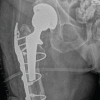

A 67-year-old female presented to the emergency department following a minor fall, reporting injury to her left lower limb. Clinical examination revealed external rotation and shortening of the left leg, with radiographs confirming a subtrochanteric fracture of left femur with features of an AFF (Fig. 1). She gave a drug history of consuming oral ibandronic acid (150 mg/month) for 7 years, as she was diagnosed with osteoporosis, indicated by a spine T-score of −3.22 on bone densitometry. In addition, the patient reported persistent right thigh pain for the preceding 3 months. Given the history of prolonged bisphosphonate use, the trivial nature of the fall, and the contralateral pain, MRI of the right femur was performed, revealing marrow edema (Fig. 2) in the subtrochanteric region, correlating with the clinical site of pain.

Recognizing the bilateral AFFs and the imminent risk of a right-sided fracture, prophylactic intramedullary nailing was performed on the right femur (Fig. 3), based on the current clinical evidence. This approach also facilitated positioning for subsequent fracture reduction and reconstruction nailing of the left femur (Fig. 4), conducted 2 days later. The postoperative course was uneventful. Bisphosphonate therapy was discontinued, and the patient was started on teriparatide injections, calcium, and vitamin D supplementation. After satisfactory post-operative X-rays (Fig. 5), full weight-bearing mobilization with walker support was initiated.